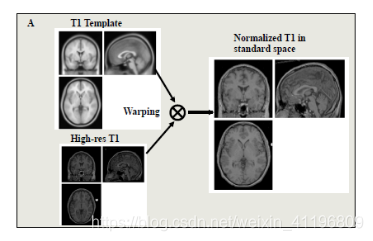

在这个模块中我们会讨论将图像与脑图谱模板(atlas template)配准及平滑(smoothing)的过程。通常来说,每个人的大脑都是不同的,两个个体的大脑尺寸差异可以达到30%,大脑形状也可能存在显著差别,所以标准化(normalization)所做的正是通过拉伸、压缩以及卷绕使得扫描得到的大脑与标准大脑模板一致。这对于组分析(group analysis)而言很重要,因为我们想要对比不同的大脑,当我们关注某一个体素(voxel)时,我们希望能够在所有被试个体的扫描图像中看到这个体素,这就需要所有的大脑“匹配”至同一个标准脑空间(standard brain space)。所以高分辨率的T1结构像现在又被配准至标准空间(normalized space),如下图2所示。

图2将高分辨率T1结构像配准至标准空间

注:从图 1的流程图中可以看出,课程中所讲的标准化是先将高分辨率的T1结构像与标准模板(此处的标准模板是高分辨率的结构像标准模板)进行配准,再直接将这些配准参数应用于功能像上(因为功能像之前已经与结构像进行过一次配准),这也是目前比较普遍的一种做法,因为T1结构像分辨率高,大脑内部结构可精准对齐。但还有另外一种做法,可以直接将功能像与标准模板(此处的标准模板是低分辨率的功能像标准模板)进行配准,这种做法在SPM软件中比较常见,不需要借助T1结构像,但在对齐效果上较差。